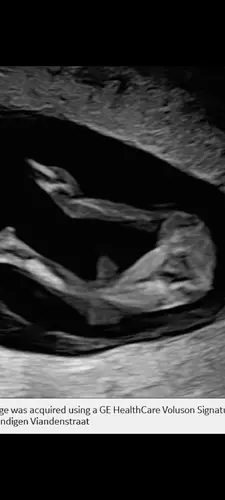

Dit is zeker een meisje hihi